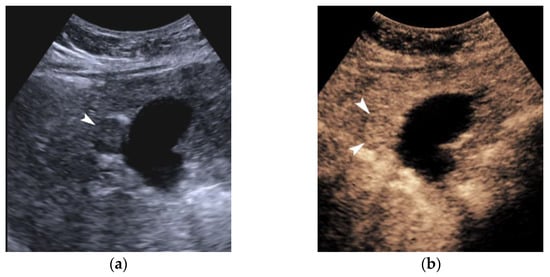

The appearances of HCC on US vary depending on the size and degree of differentiation. An important distinction in terms of size is the cut-off of 2 cm [

9]. On B-mode, HCC is hypo-echoic in more than 50% of cases, although it can be hyperechoic or of mixed echogenicity in approximately 25% of cases, respectively [

9]. Consequently, it is important not to misdiagnose a hyperechoic nodule in a cirrhotic liver as a hemangioma and discard it without further investigation. The hyperechoic element of an HCC may represent a fatty component. HCCs smaller than 1 cm can be iso-echoic, and hence difficult to detect. As a general rule, tumor echogenicity reflects cell density. Given the gradual carcinogenesis of HCC inside a cirrhotic liver, an HCC is typically nodular in shape, except for the massive type, which appears irregular. The lesion margins are usually relatively well-circumscribed in the nodular type of HCC, but poorly defined in the massive type [

9]. A peripheral hypo-echoic halo may be noted, corresponding to a thin fibrous capsule in 90% of cases [

10]. The so called “mosaic pattern” and the “nodule in nodule” appearance are two characteristic demonstrations of HCC in every modality, including US and CEUS [